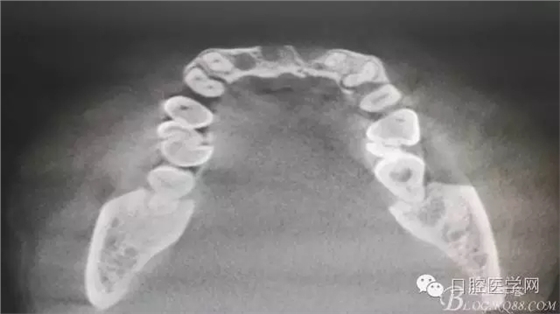

為他院轉(zhuǎn)診患者。男,無吸煙史,前牙因齲壞治療后,外力折斷導(dǎo)致拔除。現(xiàn)拔除該牙后兩個多月。 左上區(qū)域骨寬度不足,計劃植入種植體同期GBR。

左上區(qū)域骨寬度不足,計劃植入種植體同期GBR。